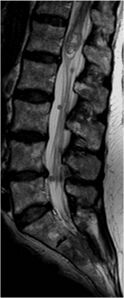

The occurrence of intramedullary tumors is relatively rare, but their treatment is often very demanding. Approximately 90% of all intramedullary spinal tumors are glial tumors, the most common of which are ependymomas (60%) and astrocytomas (30%). The third place is represented by hemangioblastomas. These neoplasias are primarily treated surgically, but there is often no possibility of complete resection due to the eloquent location and size of the tumors. Surgery and radiosurgery / chemotherapy are usually added. [4][28] náhled|MRI – spinální myxopapilární ependymom

Spinal cord ependymomas are more common in adult patients (typically between 35 and 45 years of age) and represent the majority (60%) of all primary intramedullary tumors. [4][45][46]. There are both benign, semi-minimal and malignant forms [47]. Most often, spinal ependymomas are located in the thoracic segment of the spinal cord, although they can occur along its entire length. [4].